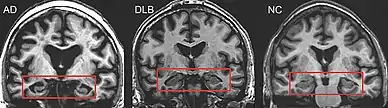

Medical imaging in AD and DLB

MRI of brain showing hippocampus atrophy (red rectangles), more prominent in AD than DLB, compared to normal control (NC)

PET or SPECT imaging can be used to detect reduced dopamine transporter uptake and distinguish AD from DLB.[57][149] Severe atrophy of the hippocampus is more typical of AD than DLB.[150] Before dementia develops (during the mild cognitive impairment phase), MRI scans show normal hippocampal volume. After dementia develops, MRI shows more atrophy among individuals with AD, and a slower reduction in volume over time among people with DLB than those with AD.[33] Compared to people with AD, FDG-PET brain scans in people with DLB often show a cingulate island sign.[33]